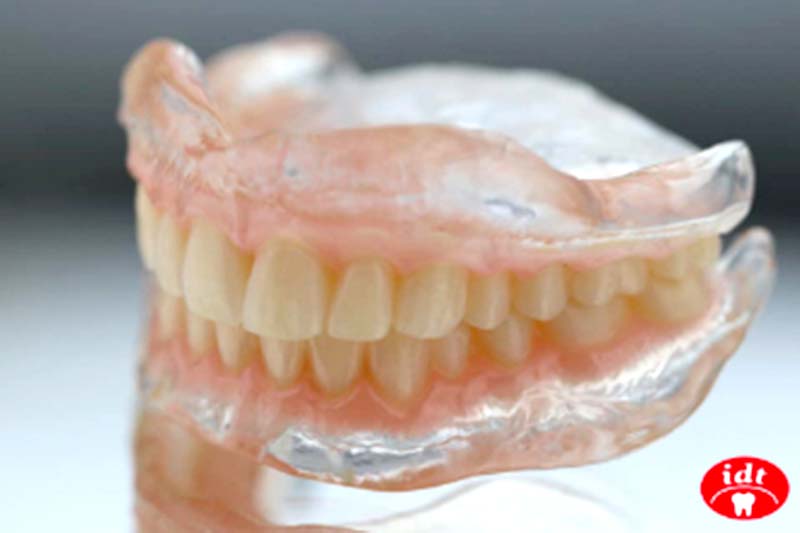

第一步|治療性義齒(BPS Denture)初期評估與口腔復健

為確保全口重建的穩定與精準,三井牙科在療程初期會讓患者配戴「治療性義齒」,這是一套經過日本JPDA假牙學會認證的義齒系統,具備以下優勢:

- 協助調整口內咬合、肌肉群、顎間關係

- 穩定牙床、修復口腔結構

- 作為醫師進行模型分析與植牙模擬的重要依據

- 這不只是過渡期的假牙,更是全口植牙重建流程中不可或缺的準備階段。